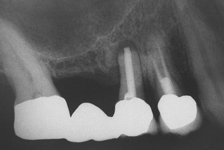

Při ztrátě molárů a premolárů v horní čelisti a jejich náhradě implantáty se často setkáváme s nedostatečnou

vertikální nabídkou kosti pod čelistní dutinou, často doprovázenou i nedostatečnou horizontální nabídkou a sníženou kvalitou kosti (v oblasti 2. premoláru v 50%, v oblasti moláru až v 80% případů nedostatečná kostní nabídka)

Od roku 1985 je tento problém řešen augmentační operací nazývanou

sinus lift.